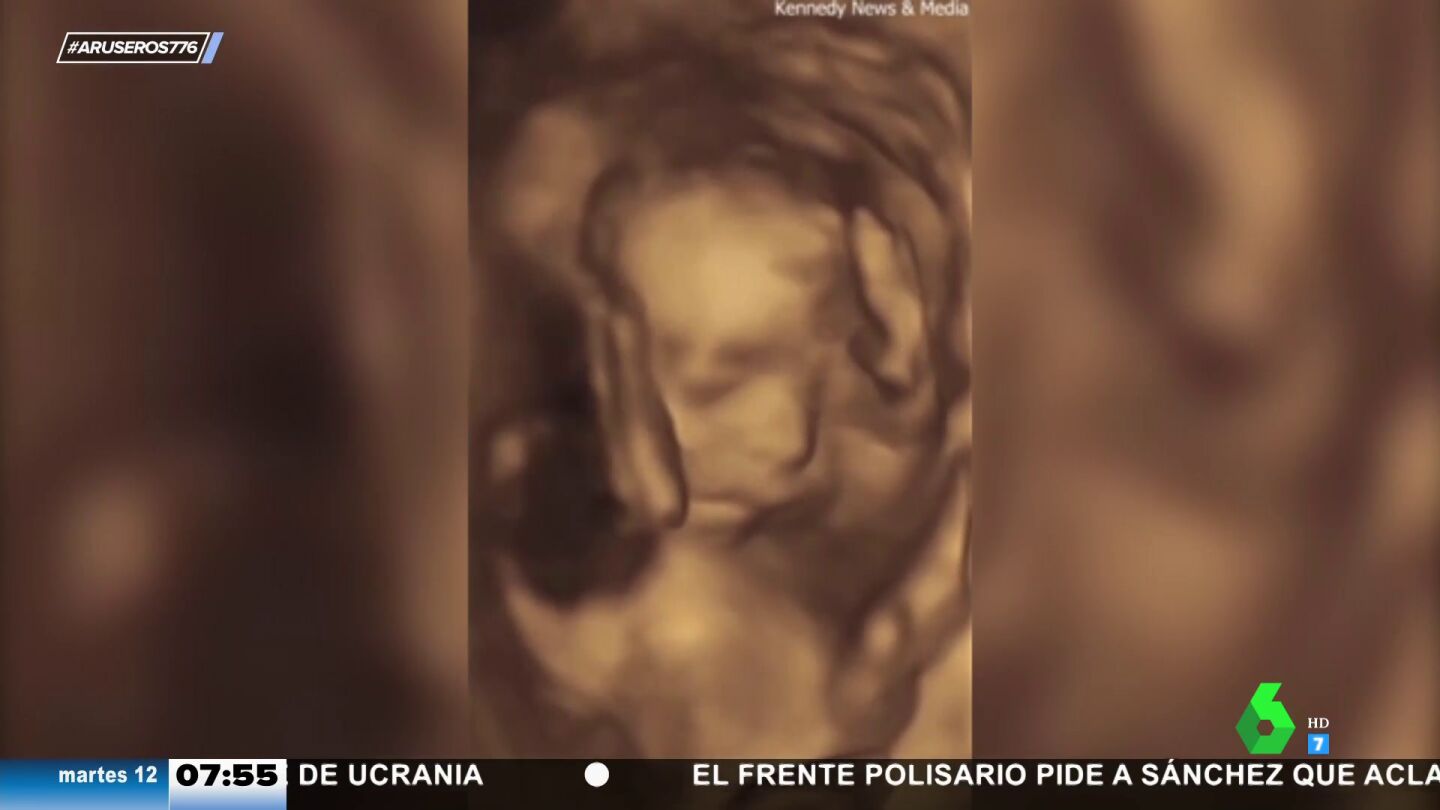

Aruser@s ha mostrado un sorprendente vídeo de una ecografía que ha compartido una madre de Pensilvania.

En el vídeo que acompaña a la noticia, grabado por una madre de Pensilvania. se muestra una ecografía grabada en la que el bebé hace un claro gesto con la mano. "Se ha visto claramente que el bebé está haciendo una peineta", ha comentado Alfonso Arús. Por si no fuera suficiente, también ha hecho otro gesto más que ha sorprendido a los colaboradores de Aruser@s.